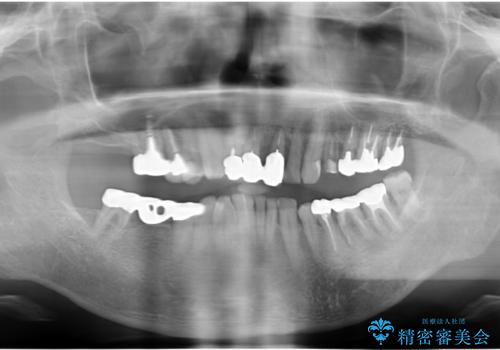

親知らずの移植 70代男性

- 70代男性

- 左下奥歯の歯ぐきから膿が腫れてきたことを主訴に来院された患者様です。

精査したところ奥歯(左下6)が破折しており、保存不可能と診断されました。

インプラント・入れ歯・自家歯牙移植(親知らずの移植)の選択肢を提案させて頂いたところ、自家歯牙移植をご希望されました。

保存不可能な奥歯(左下6)を抜歯し、機能していない親知らず(左下8)の移植を行いました。

移植後、生着を待って根管治療及び補綴修復を行いました。